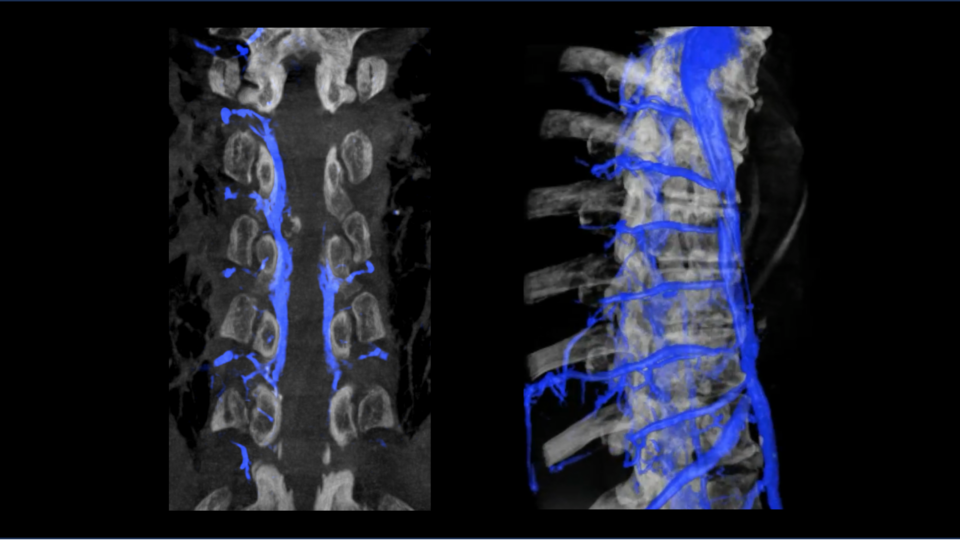

- Preoperative angiography with 3D reconstructions revealed the AVM to be 4 cm in size and at a high risk of bleeding.

Dr. Riina initially performed diagnostic and rotational angiography with 3D reconstructions (Slide 1) to better characterize the vascular pathology and to inform clinical decision-making. The detailed imaging confirmed the exact size and location of the AVM, as well as the arterial branches feeding it. The imaging also revealed several areas of the lesion featuring a high risk for potential bleeding.

In a preoperative embolization, Dr. Riina infused an ethylene vinyl alcohol copolymer dissolved in dimethyl sulfoxide into arterial branches feeding the patient’s AVM nidus. The procedure obliterated roughly 50 to 60 percent of the AVM nidus, as shown by an angiogram (Slide 3).

The following day, Dr. Riina performed an image-guided craniotomy and resection of the AVM. Intraoperative angiography confirmed the prior embolization and the successful resection of the remaining components of the AVM body (Slide 4). The patient’s migraines and visual field defects fully resolved after his surgery.